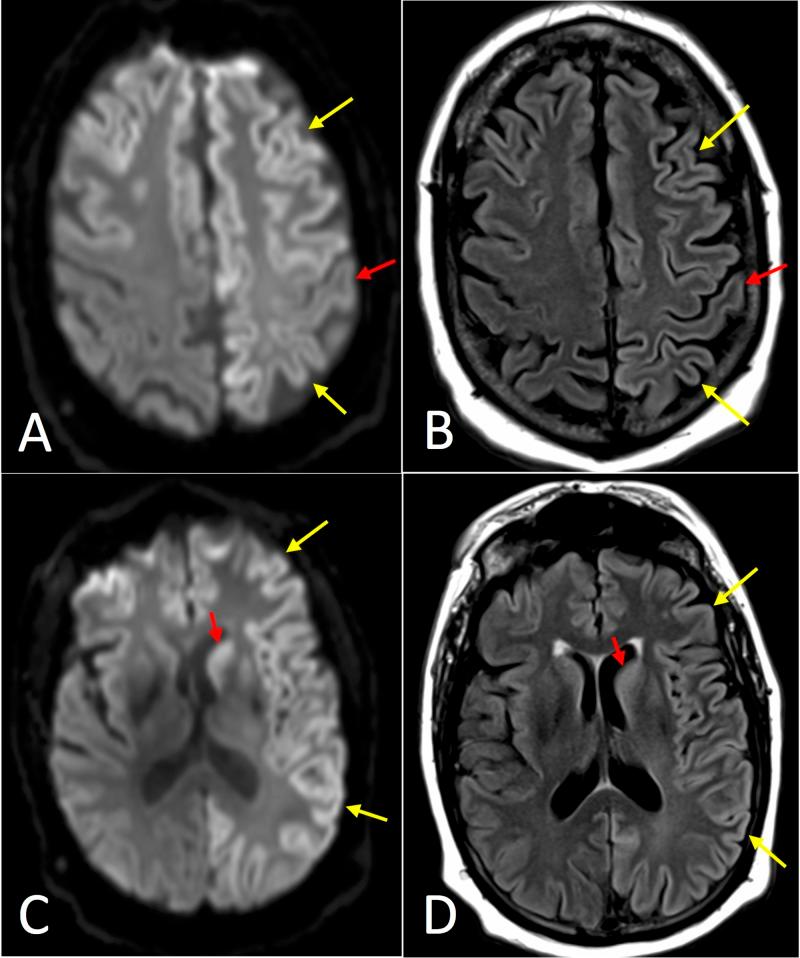

Sporadic Creutzfeldt-Jakob disease (CJD) is the most common prion disease, resulting in rapid neurocognitive decline, and is universally lethal. CJD has a confounding clinical presentation with similarities which overlap with many other neurodegenerative disorders. Brain biopsy is the current gold standard; however, less-invasive initial screening tests are also utilized. These include brain magnetic resonance imaging (MRI), electroencephalography (EEG), and cerebrospinal fluid (CSF) laboratory studies. Five patients presented to our facility with varying levels of nonspecific cognitive impairment and movement disorders. CJD was initially suggested after review of each patient's brain MRI. The T2-weighted fluid attenuation inversion recovery and diffusion-weighted images in each case demonstrated varied classic patterns of signal abnormality involving the cortex, basal ganglia, thalami, and brainstem. EEG and CSF studies were confirmatory in three and four patients, respectively (EEG not performed in one patient). One death occurred two months after initial presentation, and the other four patients were transferred to hospice three, four, nine, and 20 months after initial presentation. Radiological evaluation is an invaluable component of the workup for nonspecific neurodegenerative disorders because brain MRI may suggest the initial diagnosis of CJD, as demonstrated in our presented cases. Familiarity with the spectrum of classic MRI findings suggestive of sporadic CJD can improve radiologists' role in early detection of the most common prion disease. Clinicians may benefit from understanding the utility of the newer CSF laboratory studies (Real-time quaking-induced conversion, T-tau, and 14-3-3 protein), which are far less invasive than the gold standard of brain biopsy. Early diagnosis can help save medical resources and guide clinicians to form appropriate plans of care with the patient and family.

散发性克雅氏病(CJD)是最常见的朊病毒病,会导致快速的神经认知衰退,且无一例外会致死。CJD的临床表现令人困惑,与许多其他神经退行性疾病有相似之处且相互重叠。脑活检是目前的金标准;然而,也会使用侵入性较小的初步筛查测试。这些测试包括脑磁共振成像(MRI)、脑电图(EEG)和脑脊液(CSF)实验室检查。五名患者因不同程度的非特异性认知障碍和运动障碍前来我院就诊。在查看每位患者的脑MRI后,最初怀疑为CJD。每个病例的T2加权液体衰减反转恢复序列和扩散加权图像均显示出涉及皮质、基底神经节、丘脑和脑干的各种典型信号异常模式。EEG和CSF检查分别在三名和四名患者中得到证实(一名患者未进行EEG检查)。一名患者在初次就诊两个月后死亡,另外四名患者在初次就诊后三个月、四个月、九个月和二十个月被转入临终关怀病房。放射学评估是对非特异性神经退行性疾病进行检查的一个重要组成部分,因为脑MRI可能提示CJD的初步诊断,正如我们所展示的病例那样。熟悉提示散发性CJD的典型MRI表现范围可以提高放射科医生在早期发现这种最常见朊病毒病方面的作用。临床医生可能会从了解更新的CSF实验室检查(实时震颤诱导转化、T- tau蛋白和14-3-3蛋白)的效用中受益,这些检查的侵入性远低于脑活检这一金标准。早期诊断有助于节省医疗资源,并指导临床医生与患者及其家属制定合适的护理计划。